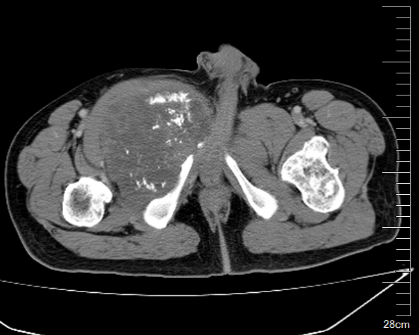

图片 2.png图片 3.png

术前CT